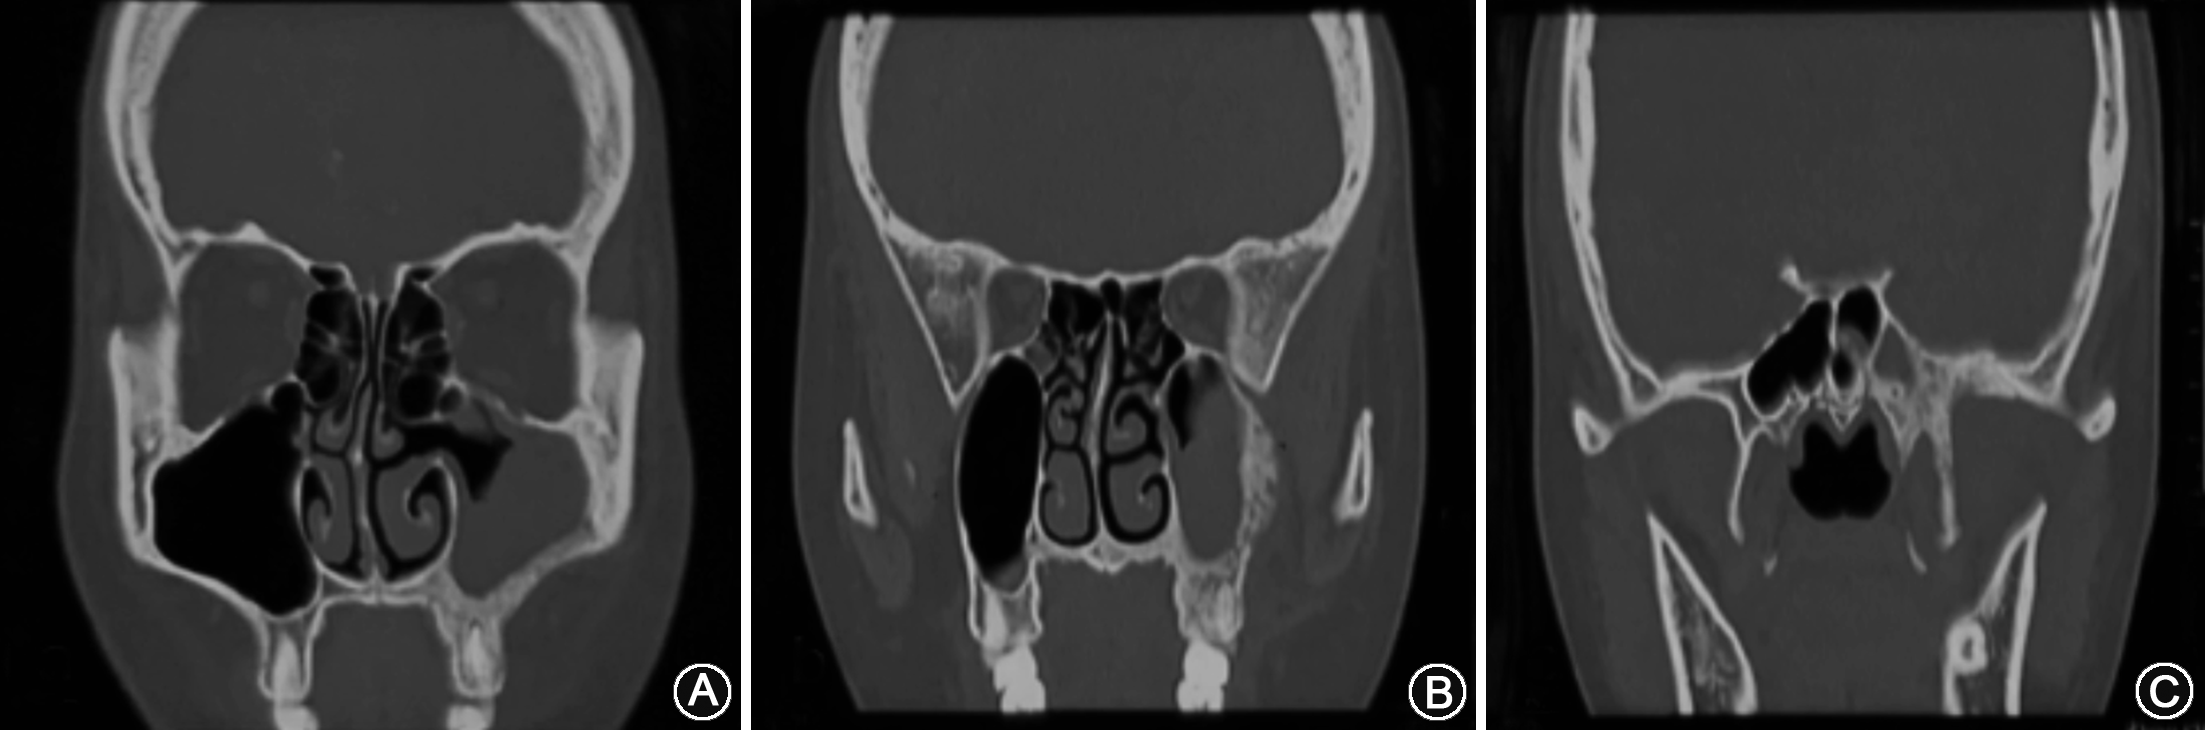

影像学检查:鼻窦部CT/MRI平扫+增强提示左侧上颌骨-蝶骨弥漫性增生硬化伴斑点状骨质破坏,周围软组织弥漫增厚肿胀,考虑左侧上颌窦炎;Paget病可能性大(图1)。全身骨密度测定以及双侧肱骨、骨盆X线检查均未见异常。

本例患者经过鼻窦炎药物及手术治疗后效果不佳,故考虑将本次治疗分为两个阶段:(1)先进行慢性鼻窦炎的综合治疗,手术清理上颌窦病变同时行上颌骨活检以明确诊断,插管全麻下行鼻内镜下经左侧泪前隐窝入路左侧上颌窦、筛窦开放术+左侧上颌骨病变活检术(图2),术后予鼻窦炎常规治疗。术后病理示:慢性鼻窦炎;(左侧上颌窦后壁组织)符合畸形性骨炎(图3)。(2)明确诊断以后转入我院内分泌科进行PDB药物治疗。予鲑降钙素注射液每天100 U皮下注射、5 mg唑来膦酸注射液单次静脉注射。